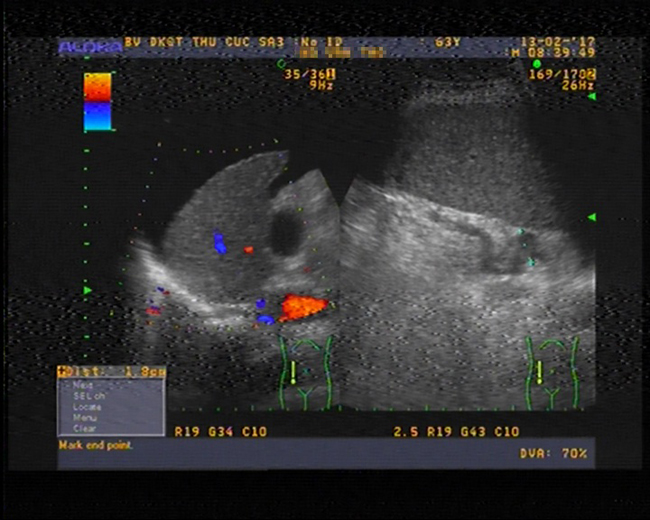

Trước khi điều trị, dịch cổ trướng của bệnh nhân N.V.T xuất hiện nhiều trong ổ bụng

Theo PGS.TS Nguyễn Xuân Thành - Chuyên gia gan mật, Bệnh viện Đa khoa Quốc tế Thu Cúc - người đã trực tiếp thăm khám và điều trị cho bệnh nhân T cũng cho hay, sau khi thăm khám và làm các xét nghiệm, bác sĩ nhận định trường hợp ông T dịch đã xuất hiện nhiều trong ổ bụng, chỉ số tiểu cầu, men gan, Albumin trong máu … ở mức thấp, sức khỏe bị ảnh hưởng nghiêm trọng.